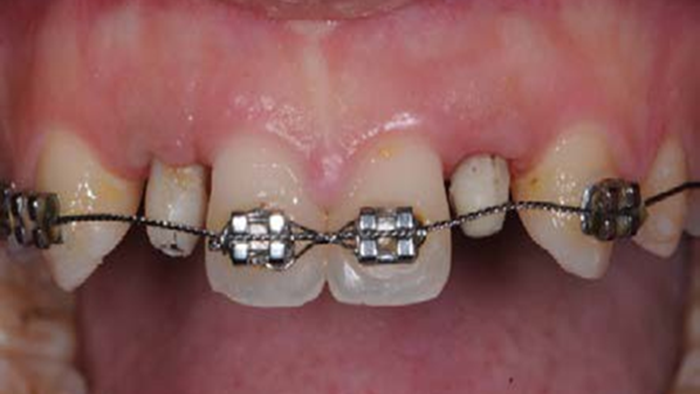

Clinical case: BPET PREDICTABILITY - State-of-the-Art SOCKET SHIELD

- Courtesy of Dr. Howard Gluckman, South Africa -

Socket Shield Technique, anterior esthetics, maxillary anterior, esthetic, esthetics, AnyRidge, Root Membrane Kit, Root Membrane Technique, Partial Extraction Therapy, PET, esthetic zone , Dr. Howard Gluckman

AnyRidge implant system, Root membrane kit, PET Kit